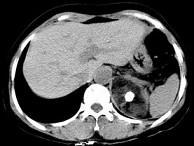

问题 男性,28岁,左腰背酸胀5个月,CT检查如图所示,应诊断为()

选项 A.左肾上腺髓样脂肪瘤 B.左肾上腺错构瘤 C.左肾上腺嗜铬细胞瘤 D.左肾上腺腺瘤 E.左肾上腺转移瘤

答案 B